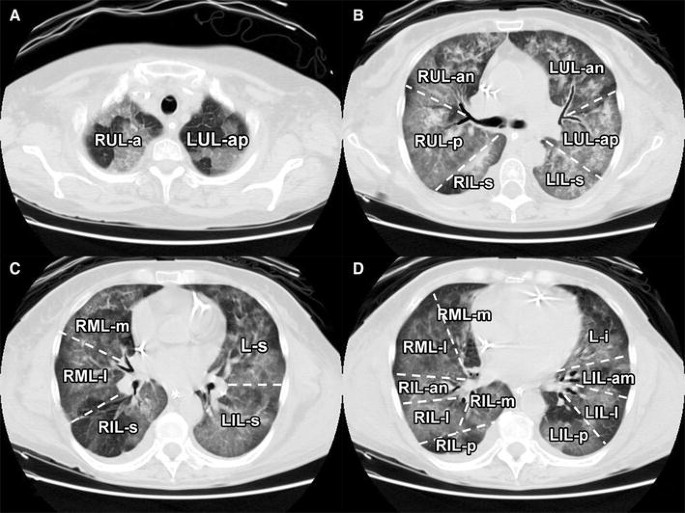

33+ Lung Segments Ct Anatomy. Each bronchopulmonary segment has its own (segmental) bronchus and arterial supply.6 segments for the left and right lung are shown in the table.4 the segmental anatomy is useful clinically for localising disease processes in the lungs.4 a segment is a discrete unit that can be. A ct was performed on a healthy subject, with an axial enhanced acquisition with different windows as the cursor is moved over an anatomical area of the lung parenchyma, the segment is highlighted and labeled: